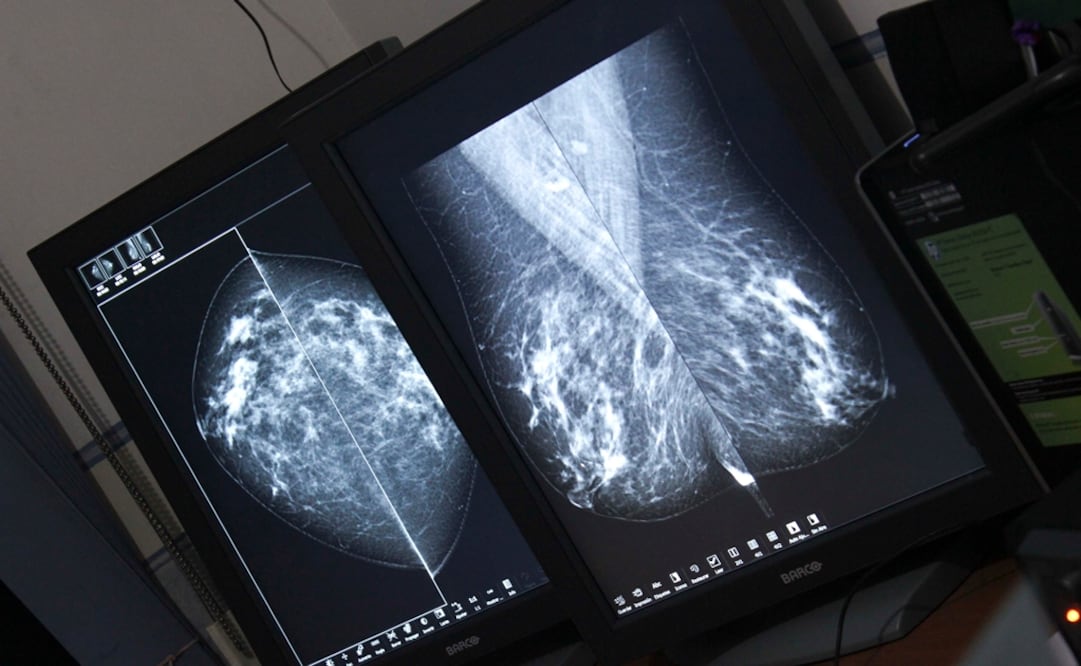

La empresa mexicana Onko Solutions diseñó un dispositivo electrónico capaz de detectar de manera temprana el cáncer cervicouterino con el fin de reducir las alarmantes estadísticas de muerte por esa enfermedad en el país, declaró hoy Héctor Torres , gerente general de la firma.

En México cada año 15 mil mujeres son diagnosticadas con cáncer cervicouterino, y unas 5 mil mueren anualmente , lo que convierte a la enfermedad en la segunda causa de muerte por cáncer en mujeres.

En México, la prueba de Papanicolaou es, desde hace 50 años, el método para detectar el cáncer cervicouterino; sin embargo, a decir de Ricardo Lúa , ginecólogo y asesor clínico de la empresa, "no es la prueba más eficaz".

Según el especialista, el Papanicolau tiene una eficacia de detección de 55 %. "De cada diez mujeres solo a cinco se les detecta oportunamente el cáncer, mientras que Instapap tiene 86 % de eficacia", aseguró.